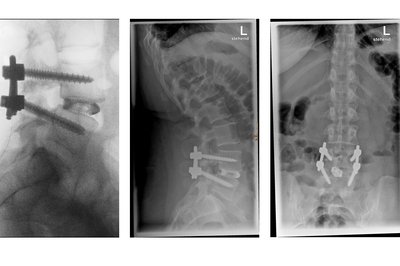

• Röntgenbild Repositionsspondylodese

Intra-operative Repositionsspondylodese am 4. und 5. Lendenwirbel

Ziel einer Fusionsoperation ist die langfristige Schmerzlinderung sowie die Erweiterung des Bewegungsradius im Alltag. Dies ist nur durch ein Fusionieren („Zusammenwachsen“) der operierten Wirbelkörper zu erreichen. Die Bandscheibe wird entfernt und durch einen Titanblock sowie Knochenmaterial ersetzt. Ein Gerüst aus Titan-Schrauben und Stangen hält die Wirbelkörper in der richtigen Stellung. Darüber hinaus müssen Spinalkanalstenosen entfernt und Nervenwurzeln befreit werden, um die hiermit verbundenen Schmerzen dauerhaft zu lindern. Über mehrere Monate hinweg wachsen nun die Wirbel zusammen und bilden eine Einheit. Die Plazierung der sogenannten Pedikelschrauben für Stabilisierende Operationen erfolgt in unserem Haus ausschließlich in navigierter Technik. Dies bringt eine größtmögliche Sicherheit für den Patienten sowie eine exakte Schraubenlage.